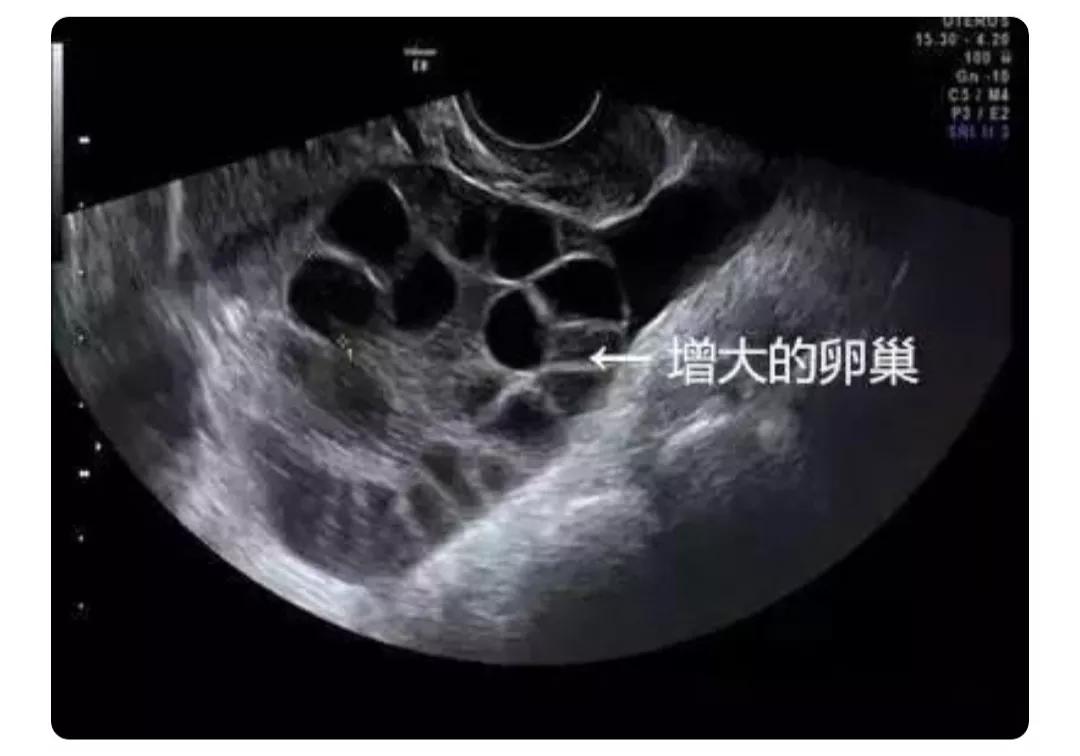

要捐卵必须得打促排针,促排卵针打得过多会引起“卵巢过度刺激综合征”,并且会引起腹部积水。

卫生条件不达标会引起阴道感染。

取卵次数过多还会引起不孕不育,卵巢早衰,不能维持青春模样,遗憾一生。要知道,女人一生中的卵子是有限的,不像男人的精子无穷无尽,女人一生只能排300—400个卵,一旦排完了就会导致早衰和绝育。